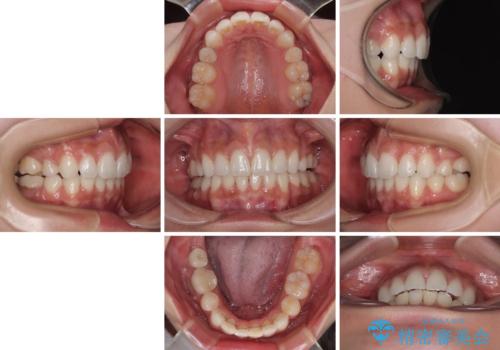

膨らんだ口元を改善する抜歯矯正 インプラント治療も同時に行う総合歯科治療

- 口元の突出感を気にして来院された患者様です。

左右ともに奥歯の咬み合わせに問題があり、上顎臼歯が前方位にある状態で、結果として上顎前歯全体が前方位かつ叢生になっていました。

補助装置を用いて上顎歯列全体を後方に移動させ、下顎は左右で抜歯する小臼歯を変えることで、左右の咬み合わせをより理想的な位置となるように計画しました。